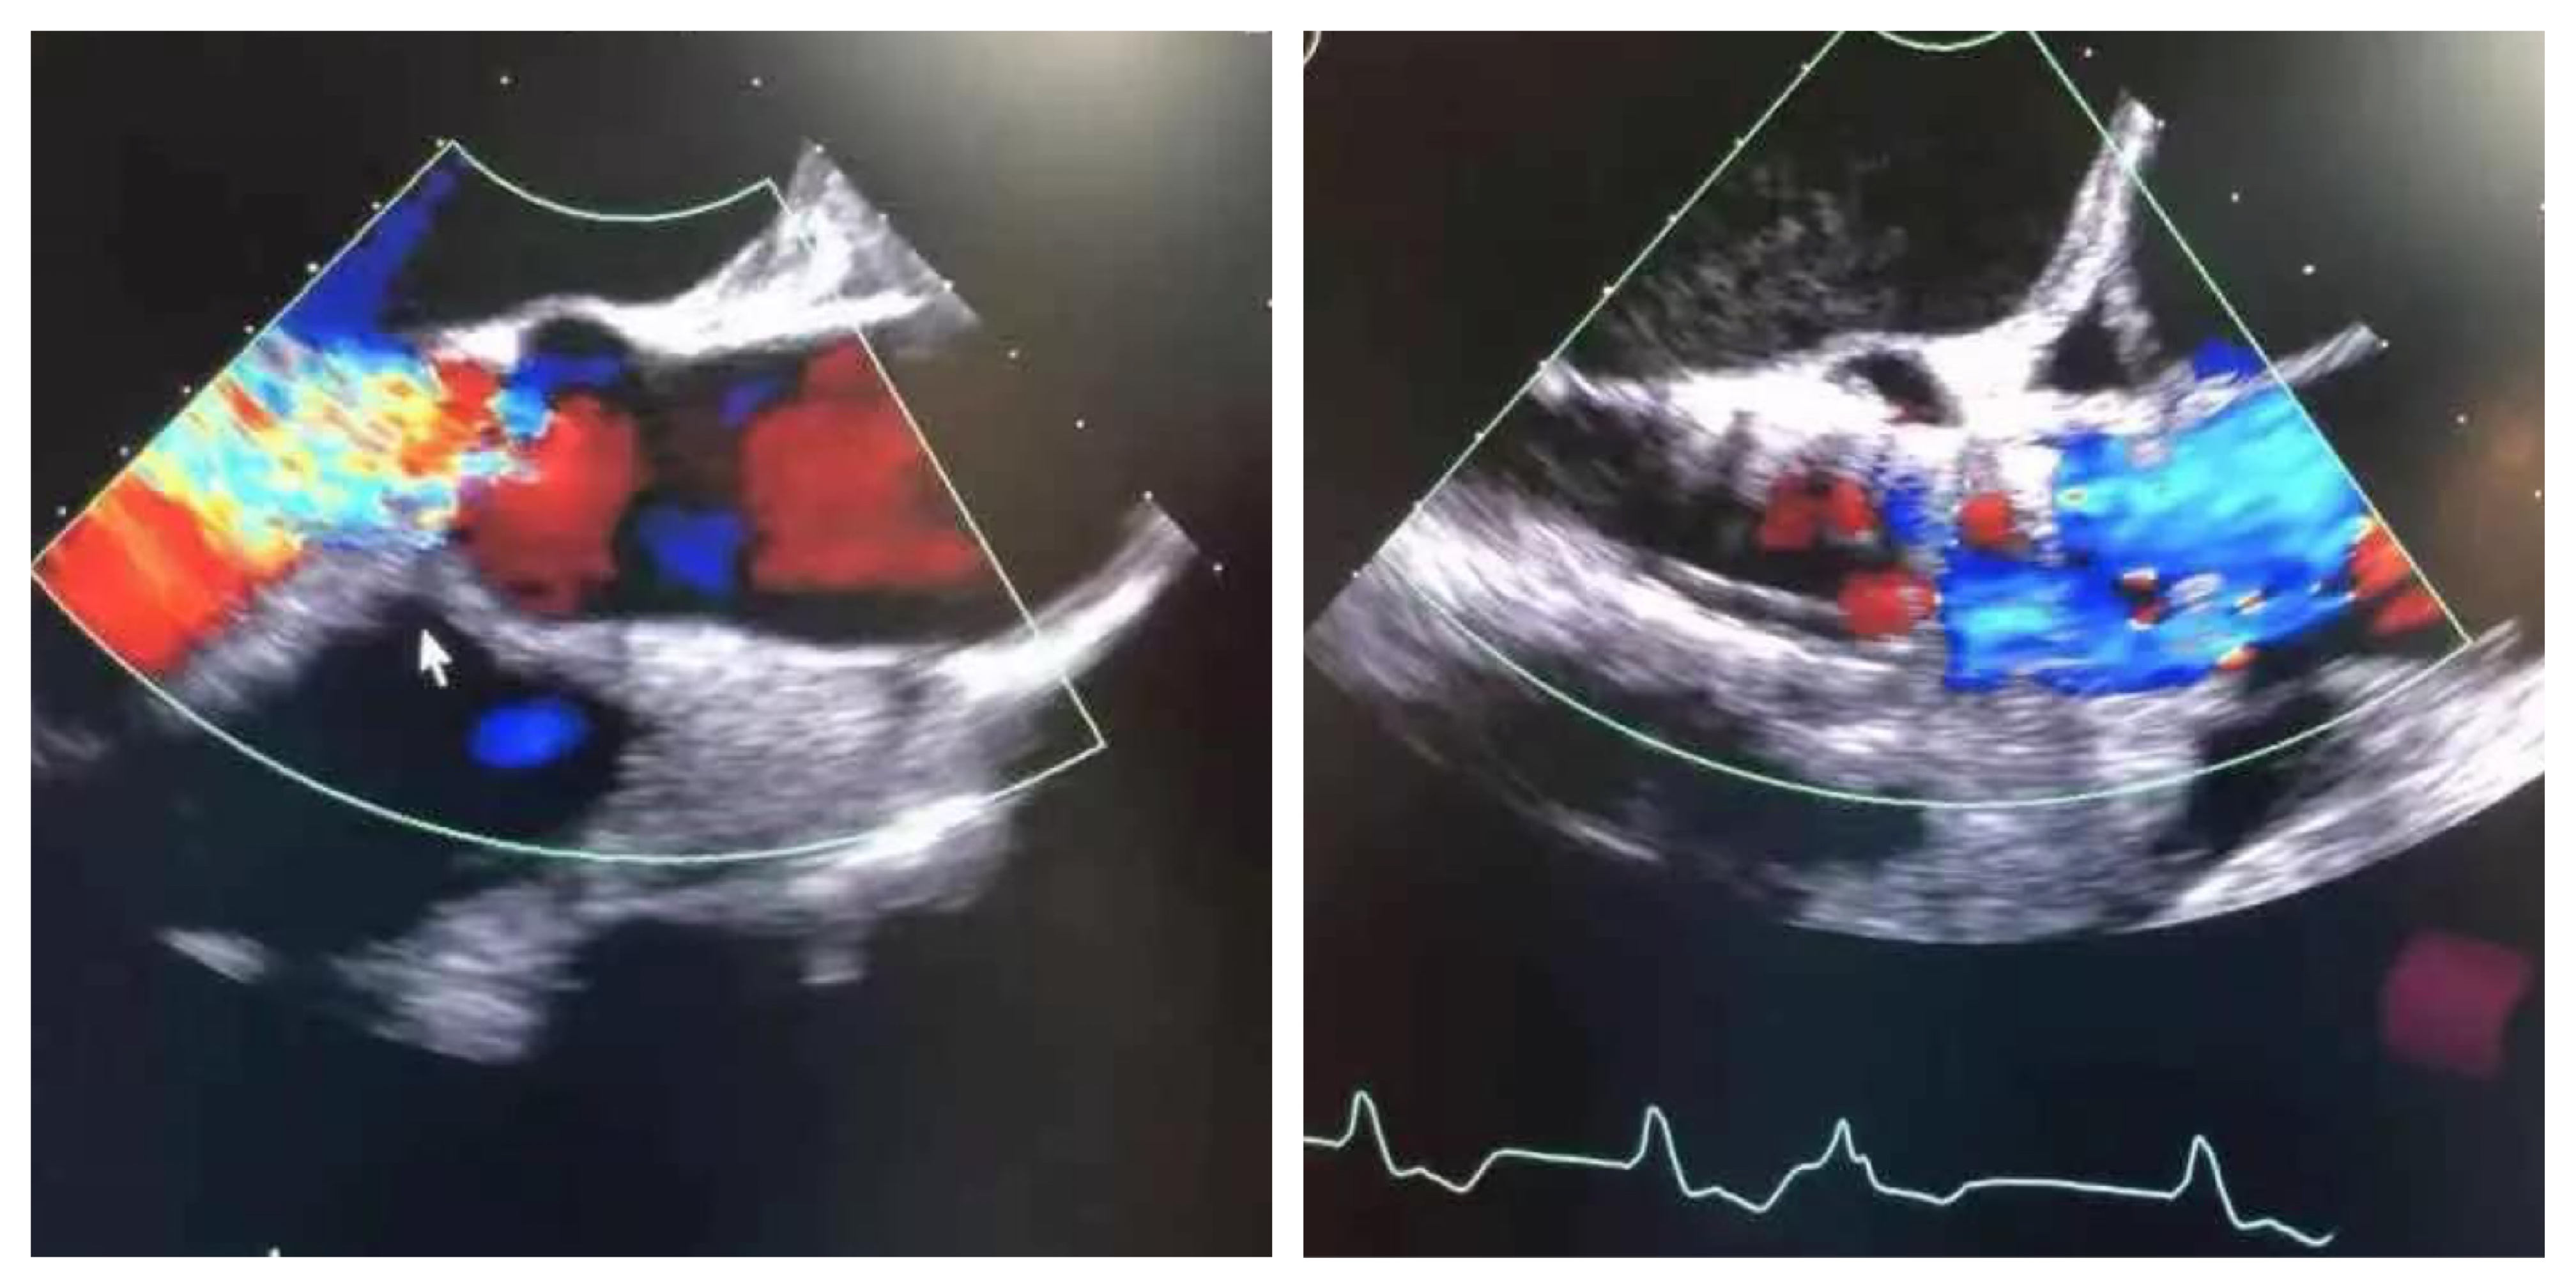

术前心超 术后心超

术后即刻:微量瓣周漏,舒张压明显改善至69mmHg。